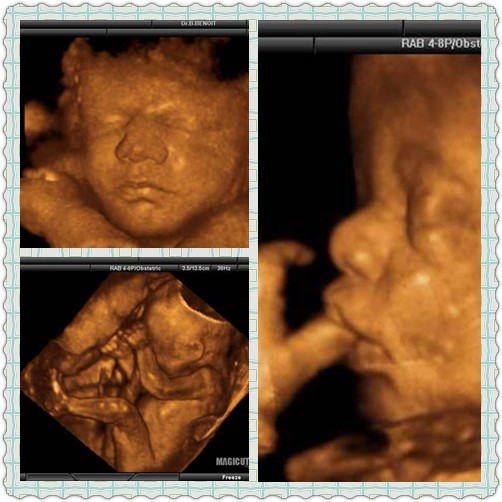

功能科現(xiàn)有醫(yī)務(wù)人員17人,主任醫(yī)師1人,副主任醫(yī)師2人,主治醫(yī)師4人,醫(yī)師8人,副主任護師1人,護師1人。碩士研究生3人。副教授及講師10人,承擔(dān)著醫(yī)學(xué)院影像及臨床專業(yè)20%的教學(xué)任務(wù)。 功能科下設(shè)有5個彩超室、經(jīng)顱多普勒、腦電及心電室。科室擁有GE—logiq E9、GE—voluson730(四維彩超)、西門子彩超等先進設(shè)備。 四維超聲是目前世界上最先進的彩超設(shè)備,我科在全市最先引進了四維彩超儀。通過四維彩超,準(zhǔn)父母們能親眼目睹胎兒寶寶的容貌和動作,更為重要的是四維彩超能夠多方位、多角度地觀察宮內(nèi)胎兒的生長發(fā)育情況,為早期診斷胎兒先天性畸形提供準(zhǔn)確的科學(xué)依據(jù)。  超聲引導(dǎo)下介入治療也是我科在牡丹江地區(qū)較早開展的一項超聲技術(shù),對于經(jīng)皮經(jīng)肝超聲引導(dǎo)下膽道置管引流(PTCD—治療各種原因引起的梗阻性黃疸)、超聲引導(dǎo)下乳腺小結(jié)節(jié)術(shù)前細(xì)針穿刺定位、肝血管瘤硬化治療、超聲引導(dǎo)下腫物穿刺活檢、肝、腎、卵巢囊腫的超聲引導(dǎo)下介入治療等技術(shù)已經(jīng)有豐富的臨床積累。

四維超聲彩超設(shè)備 |